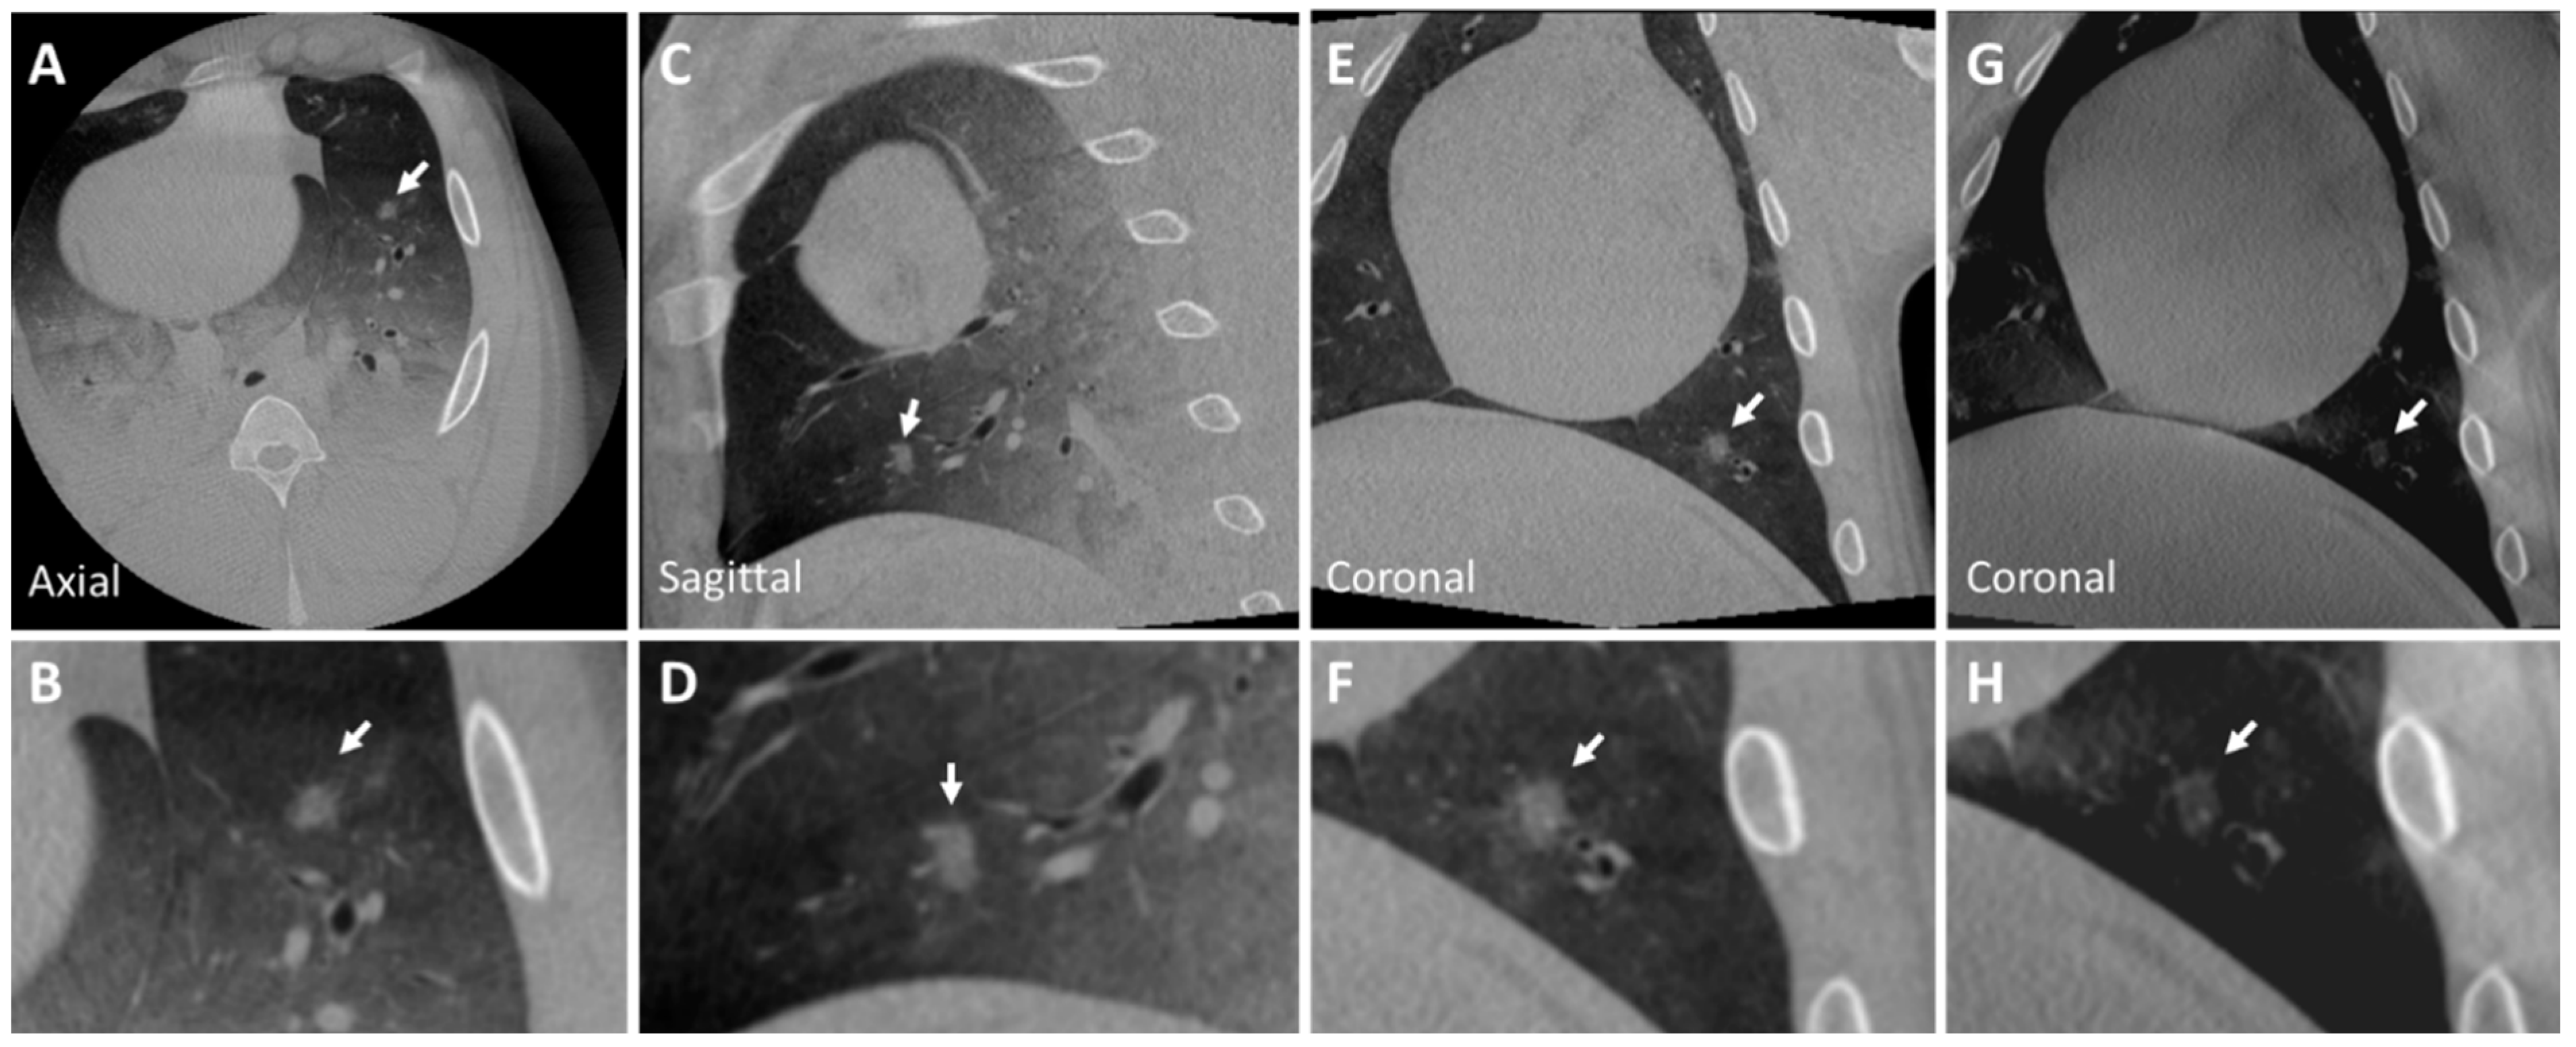

3.2. Post-Mortem Swine Lungs